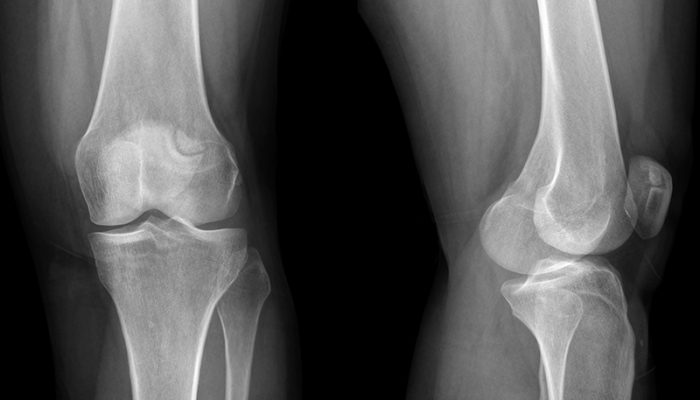

Рентгенография

С ее помощью достаточно легко можно заметить изменения костных структур. Особенно – при большом сроке болезни. Исследуются пораженные суставы.

В литературе описан и хорошо известен рентгенологам симптом «пробойника». Заключается в том, что в области суставных головок обнаруживаются округлые дефекты костной ткани, где обычная структура костей нарушена из-за отложений уратов.

Диагностическая ценность этого метода на начальных стадиях болезни сомнительна, так как симптом «пробойника» начинает визуализироваться после 6–12 лет болезни.